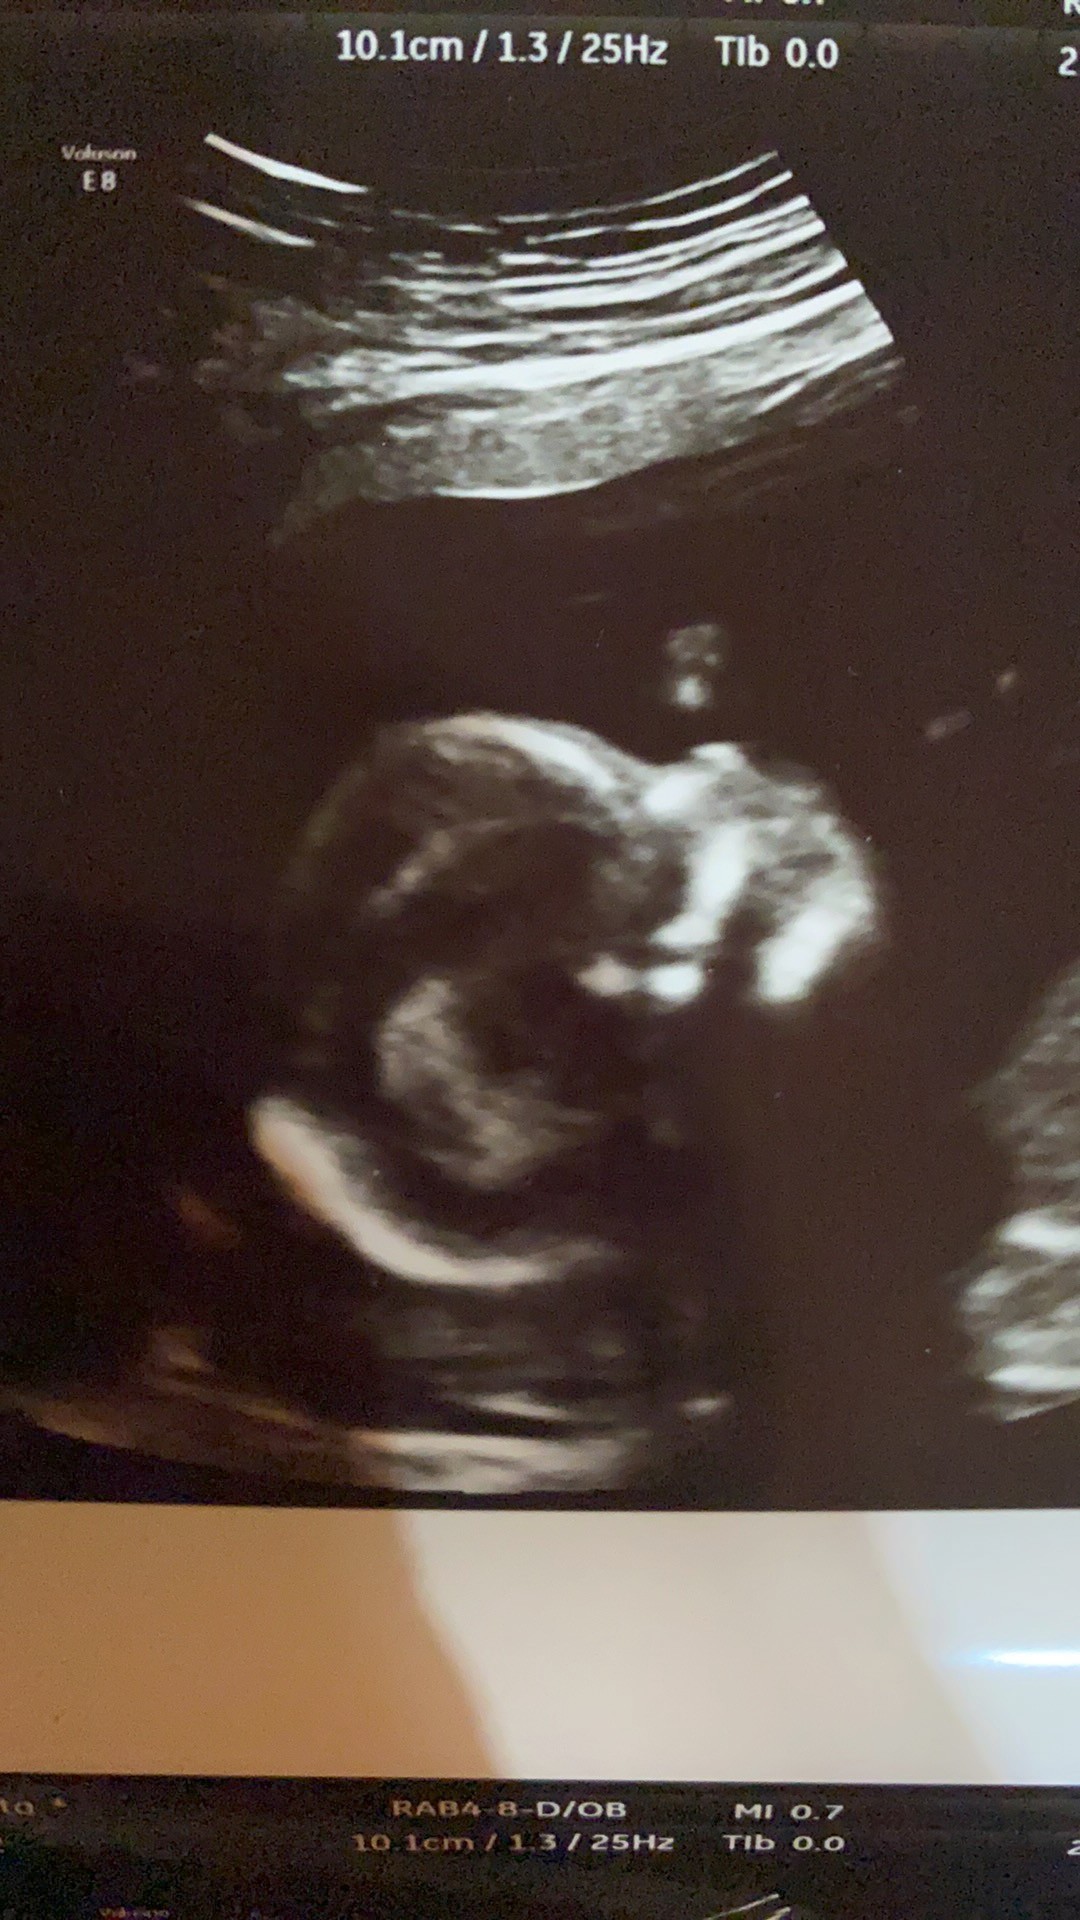

Ja po wizycie wszystko dobrze, uf. Lekarz daje 90% pewności, ze będzie dziewczynka wiec nastawiam się już na córeczkę. 🥰 malutka ma niecałe 13 cm i wazy 162g.

Ale byłam zaskoczona, ze aż tak dobrze widać kręgosłup małej😮